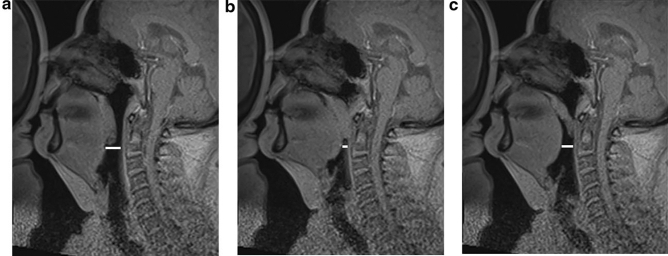

Obstruction, also synonymous with collapse or narrowing, was defined differently in among studies. Obstruction in the majority of the studies was defined as the disappearance of the airspace in the RP or RG area in the sagittal, and axial planes if applicable [26, 28, 29]. Moon et al. and Barerra et al. defined a > 50% reduction in length in the sagittal plane and whereas Huon et al. defined a > 75% reduction in length in the sagittal plane as obstruction [20, 24, 30]. Lee et al. used a classification of no obstruction, partial obstruction, and complete obstruction [31]. A 50% reduction in length, if assumed to be circumferential, would increase airflow resistance by a factor of 16 according to Poiseuille law [32]. Kavcic et al. reported 25% RG narrowing using specific measurements in the axial plane as obstruction if associated with an apneic event, whereas Berrera et al. reported a 50% change in RG anterior–posterior dimension as a positive obstruction as judged by the two interpreters without using specific measurements to quantify a 50% change [26, 30]. The subjective interpretation of obstructions was shown to have good inter-rater reliability in the RP area, but some variability was reported in the RG area [30]. Obstruction in the meta-analysis was adapted using the criteria as defined by each study. Figure 2 demonstrates an example of RP and RG obstruction as seen on imaging. NP obstruction was not seen in any patient. RP obstruction was found in 157 of 160 (98.1%) patients, RG obstruction was found in 65/160 (40.6%) patients, and HP obstruction was found in 8/160 (5%) patients. LPW collapse was only recorded in studies including axial or coronal planes and was found in 35/73 (48%) patients. Multi-level obstructions were also reported. The combination of RP + RG was found in 38/160 (23.8%) patients. The combination of RP + RG + LPW was found in 25/73 (34.2%) patients. Nine patients exhibited RP and LPW, 4 patients exhibited RP + HP, and 3 patients were found to have RP + RG + HP (Table 2).

Fig. 2.

This image demonstrates (A) Patent airway (B) Retropalatal obstruction with retroglossal narrowing (C) Retropalatal obstruction without retroglossal narrowing. All images taken on midline sagittal view using dynamic sleep MRI. This image is from Sleep magnetic resonance imaging with electroencephalogram in obstructive sleep apnea syndrome, Kavcic et al. [26], reprinted with permission from Wiley